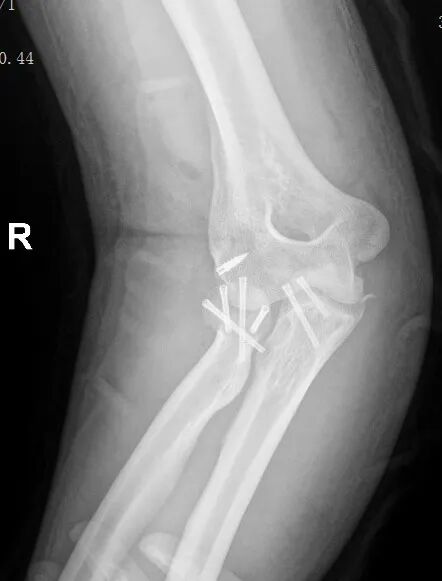

黄益平主任接诊后,经详细询问病史、查体并完善相关检查后,明确诊断为 “右肘关节恐怖三联征( 右尺骨冠突骨折、右桡骨小头粉碎性骨折 、肘关节后脱位已复位)”。

患者术前影像

恐怖三联征

“恐怖三联征, 是肘部最复杂的高能量创伤之一 ”,黄益平主任介绍,该病症因涉及骨性结构与软组织的复合损伤, 治疗难度极大, 若处理不当易导致关节僵硬、不稳定、创伤性关节炎等后遗症,甚至可能造成永久性功能障碍。